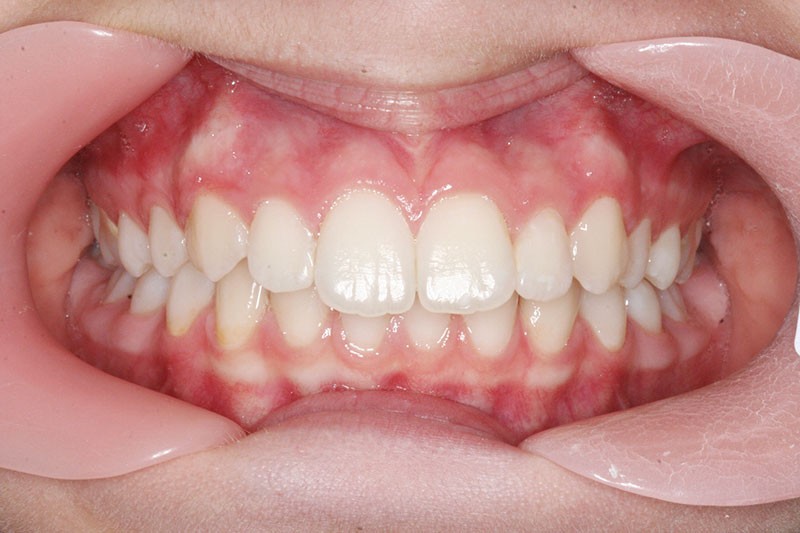

Nous sommes en présence d’une patiente adolescente âgée de 12 ans ½ dans une phase de croissance faciale favorable.

Elle présente une classe II squelettique par rétrognathie mandibulaire et une classe II dentaire molaire et canine droite et gauche associée à une biproalvéolie incisive maxillaire et mandibulaire.

L’environnement vertical est normodivergent.

Le contexte facial est délicat avec un profil cis-frontal, un angle naso-labial très ouvert et un sillon labio mentonnier marqué avec retour de la lèvre inférieure en arrière des incisives maxillaires.

Le pronostic de correction de la classe II est favorable mais il est très important de souligner la vestibuloversion incisive mandibulaire et le risque parodontal associé (fig. 1 à 3).